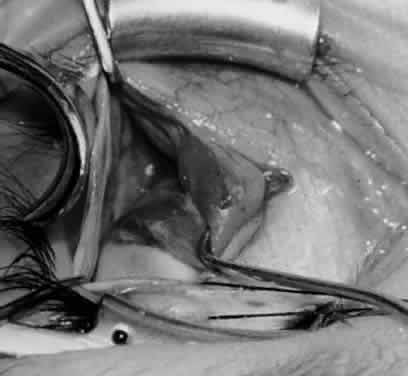

Fig. 33. A 6-0 Vicryl suture is placed in the inferior oblique muscle in preparation for anterior transposition. A Green muscle hook is placed beneath the inferior rectus muscle.

Fig. 34. The eye is retracted nasally with a Green muscle hook. The anterior suture is placed just anterior and temporal to the insertion of the inferior rectus muscle. The posterior suture is applied about 10 mm temporal to the inferior rectus muscle on a line that would be continuous with the inferior rectus insertion if it were extended temporally.

Fig. 35. The suture is tied, and the inferior oblique muscle is in the position for anterior transposition. The inferior rectus muscle is retracted nasally on the Green muscle hook, and the Desmarres lid retractor is placed inferior temporally.